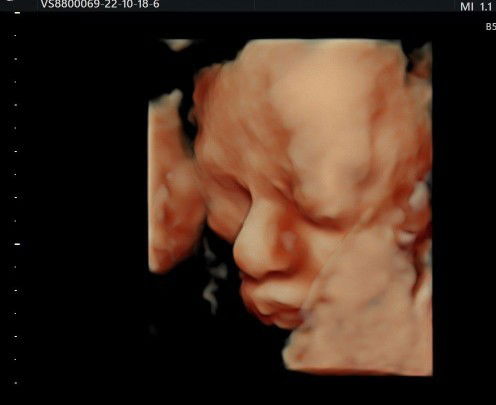

Soon to be a mom. ❤️

3D Ultrasound #Boy

Yey! Skl po. Nakapag pa 3D na kami ng baby (950 pesos lang). Tangos ilong ng mahal namin, kaso nasa tyan ka palang mukha ka ng masungit at tahimik haha.